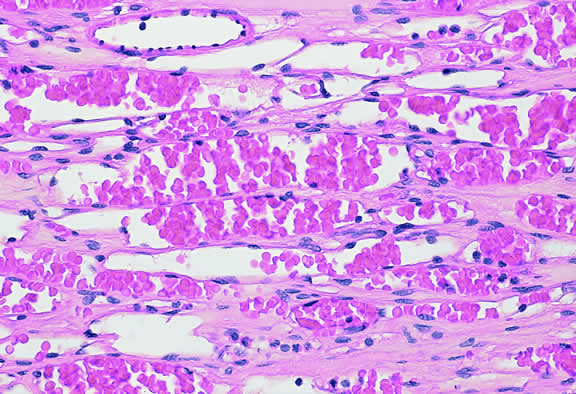

Leukemia

Secondary ocular involvement is relatively common in patients with advanced leukemia; Leonardy and coworkers199 found ocular involvement in 31% of 135 eyes obtained postmortem from leukemic patients. Ocular tissues may involved primarily by infiltrates of leukemic cells or secondarily by manifestations of the disease including hemorrhage, ischemia, or secondary infection related to primary immunosuppression or the effect of immunosuppressive drugs.200,201 Although leukemic cells can infiltrate almost any ocular tissue, choroidal infiltration occurs most often. Kinkaid and Green201 found some degree of choroidal infiltration in 65% of 367 pairs of postmortem eyes from leukemic patients examined histopathologically. Significant choroidal involvement often is accompanied by a shallow serous retinal detachment at the posterior pole. Secondary retinal changes include retinal hemorrhages, white centered hemorrhages, cotton-wool spots, nonperfusion, vitreoretinal neovascularization, and central retinal vein occlusion. Vitreous and choroidal hemorrhage also may occur. Infiltration of the optic nerve may produce an optic neuropathy.202–204 Iris infiltration may manifest clinically as iris heterochromia, a pseudohypopyon of leukemic cells, or hyphema.